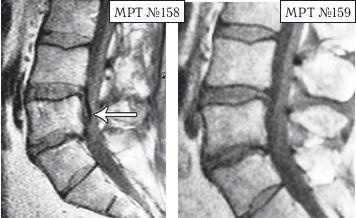

Следующий случай также по-своему уникален. Это ещё одно прямое свидетельство широкого спектра возможностей вертеброревитологии в решении задач, многие из которых на современном этапе медицины считались неразрешимыми.

На МРТ № 158 наблюдается состояние поясничного отдела позвоночника после хирургической операции в сегменте LV—SI и образовавшаяся секвестрированная грыжа межпозвонкового диска в сегменте LIV-LV с каудальной (вниз) миграцией секвестра вдоль тела позвонка LV, сужение просвета спинномозгового канала (стеноз).

На МРТ № 159 — состояние поясничного отдела позвоночника после лечения методом вертеброревитологии: отсутствие грыжи межпозвонкового диска в сегменте LIV-LV, ширина в данном участке спинномозгового канала восстановлена до естественной его нормы.

Конечно, с позиции наблюдателя, неискушённого в тонкостях вариабельности различных коварных патологий, МРТ № 158, после вышерассмотренных грыж значительных размеров, мягко говоря, не впечатляет. Но специалисты, надеюсь, прекрасно понимают, насколько это сложный случай, даже по сравнению с эпизодами наличия больших секвестрированных грыж. Думаю, что подробности этого случая будет интересно узнать также и вам, уважаемый читатель. Дело в том, что у данного пациента по природе довольно суженный спинномозговой канал, то есть, говоря медицинским языком, наблюдается стеноз спинномозгового канала первого типа (врождённый). А здесь ещё и такое осложнение: длительная локализация секвестра грыжи вследствие постоянных воспалительных процессов вызвала гипертрофию задней продольной связки и своеобразно «подпаялась» к ней. Таким образом, подобная патология (секвестр) значительно усугубила ситуацию: практически на 50 % дополнительно сузила и так изначально врождённый узкий спинномозговой канал. Естественно, у пациента появились боли и слабость в обеих ногах.